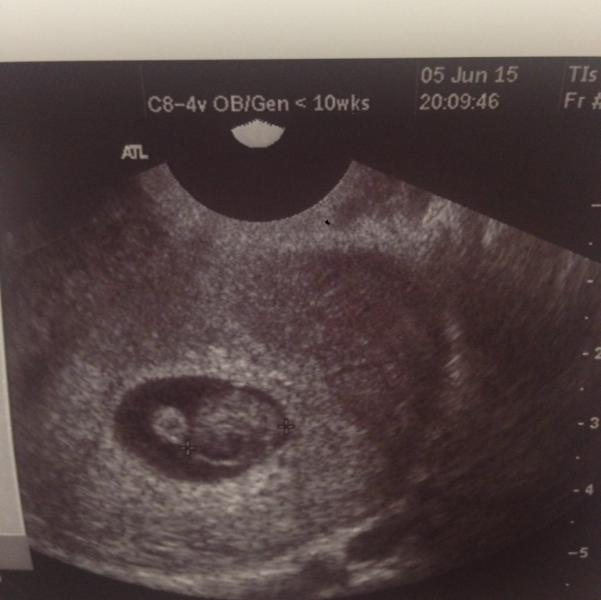

А я сегодня была на узи... "А вот и ваша лялечка...." 🙈🙈🙈🙈😌

Сказали почти 8 недель 😳.. Гиня же мне доказывала, что типо недель 5 еле..но я ж тоже знаю, что это невозможно...😁

В общем, о какие мы уже... Ааааа😱☺️☺️☺️ 150 ударов в минуту.. И 14 мм👶🏼

Ах... ☺️ 2 месяца почти.... Аааа!!!! И пусть весь мир подождет.. 🙈💞💞💞💞💞